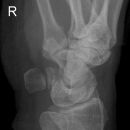

Handgelenk seitlich

Beurteilungskriterien

• Neigung der distalen Radiusgelenkfläche in der Sagittalebene: 10 – 15°

• Kontinuierliche Verlängerungsachse durch Radius, Lunatum, Capitatum und Os metacarpale III. Kontinuität von Handrücken und Unterarmrückfläche (Luxation, nicht-exakte Einstellung? -> Proc.styloideus ulnae im hinteren Radiusdrittel?)

• Scapholunärer Winkel 30 – 60°

• Verstreichen und Ventralverlagerung der volaren Fettstreifen vor dem M.flexor digitorum profundus und M.pronator quadratus

• Grundsätzlich gilt: unklare Verhältnisse -> CT-Indikation